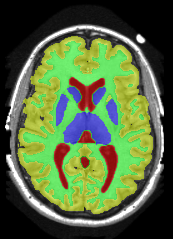

| ground truth | a-exp[7, 8] | QPBO [25, 8] | ours |

We extend [8], which introduced HINTS for arbitrary trees. In [8] a-expansion (a-exp) [7] was used to optimize the multi-label formulation of HINTS, but it often results in bad local minima due to complexities of interaction constraints, e.g. Fig.2. The contribution of [8] is a binary multi-layered HINTS formulation. They use high-order data terms, which are not easy to convert into unary and pairwise potentials for arbitrary trees. Their algorithm’s global optimality guarantee depends on the tree at hand. Only trees that do not yield frustrated cycles [25] have this guarantee, but this is not immediately obvious for any given tree. In [8], non-submodular binary energy implied by frustrated cycles were addressed by QPBO [25]. In practice, QPBO produces only partial solutions for most trees, see Figs. 2, 15 and 17.

3 Optimization

In Section 3.1 we introduce our Path-Move algorithm and in Section 3.2 we show which interaction constraints Path-Move could optimize. The authors in [8] showed that HINTS is non-submodular for a general tree and they used either QPBO or a-exp for optimization. Unfortunately, QPBO does not guarantee to label all pixels and we observed that in our experiments, see Fig. 2. The a-exp algorithm [7] is guaranteed to label all pixels but prone to weak local minima, Fig. 2.